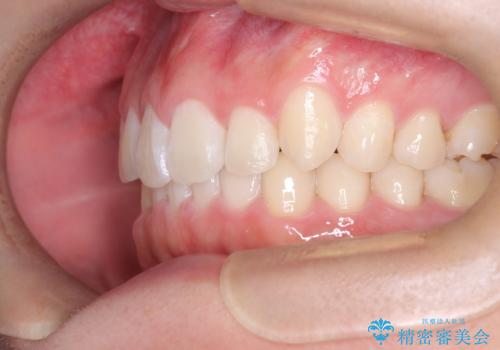

- 歯のデコボコと過蓋咬合を主訴に来院された患者様です。

アーチの拡大とIPRを行い非抜歯で治療を行いました。

歯を抜かずに叢生(デコボコ歯列)と過蓋咬合を改善する事が出来ました。

インビザラインによる治療でも十分に美しい歯並びを実現でき、患者様にも大変ご満足いただけました。